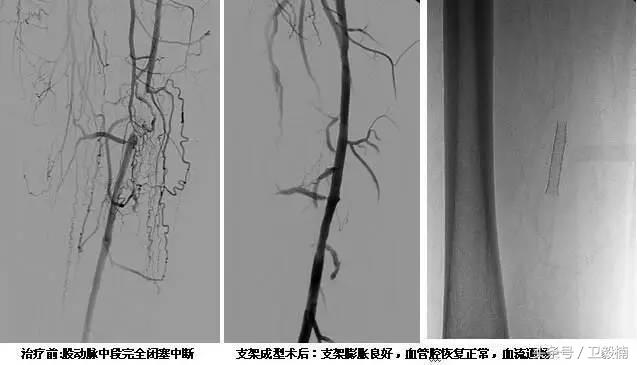

60年*开代**始应用于动脉,使狭窄的血管扩张,70年代研制双腔气囊导管成功后,得到广泛应用,多用于髂、股、腘动脉及肾动脉。肾动脉PTA(或PTPA)多用于肾源性高血压,使狭窄肾动脉扩张,从而降低血压。PTA亦可用于冠状动脉,称为经皮腔内冠状动脉成形术(Percutaneous transluminal coronary angioplasty,PTCA),使硬化的冠状动扩张,以达到治疗冠心病的目的。PTA使用的导管为带胶囊的双腔导管,将胶囊段置于狭窄血管处,囊内注入含有造影剂的液体,加压至3~6个大气压,每次持续10—15o。加压可重复3~4次,多数能使狭窄血管达到扩张的效果。

PTA多用于动脉粥样硬化性狭窄的血管,其机理是粥样斑块受压,内膜和中层撕裂、伸展,使管腔增宽。其他原因的血管狭窄,如多发性大动脉炎,先天性血管狭窄,有时也可用PTA治疗。

(1)PTA +Stent治疗血管狭窄。

(2)溶栓+PTA和(或)Stent治疗血管狭窄。